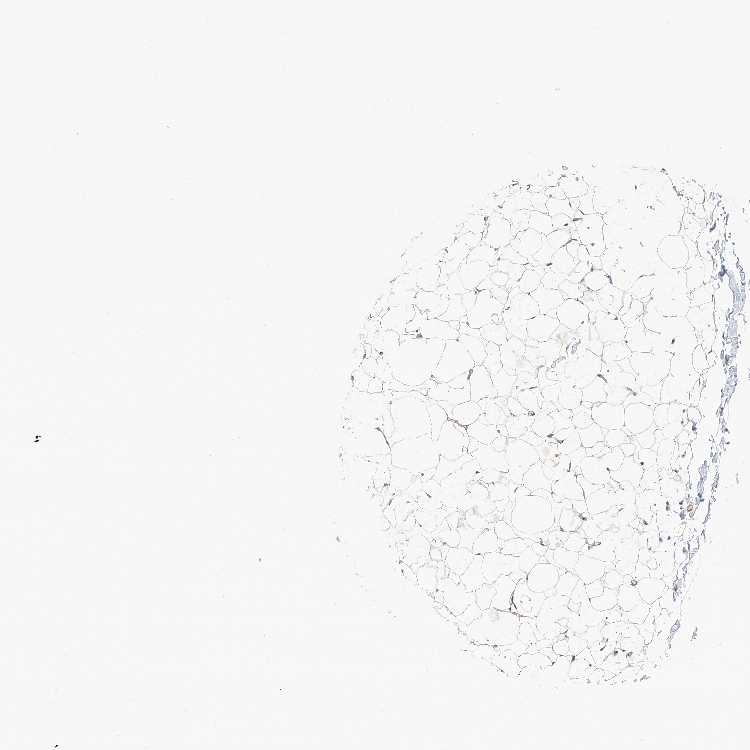

SOFT TISSUE 1 - Antibody stainingi

Antibody staining in the annotated cell types in the current human tissue is reported as not detected, low, medium, or high, based on conventional immunohistochemistry profiling in selected tissues. This score is based on the combination of the staining intensity and fraction of stained cells.

Each image is clickable and will lead to virtual microscopy that enables deeper exploration of all samples and also displays staining intensity scores, fraction scores and subcellular localization as well as patient and tissue information for each sample.

Antibody HPA030220

Chondrocytes Low

Fibroblasts Not detected

Peripheral nerve Not detected